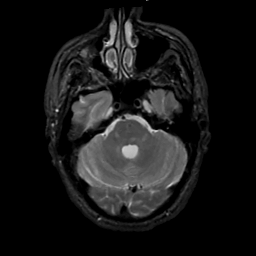

MR Study #1, February 10, 1991 -- Slice #13

[Home][Help][Clinical][Tour 1][Tour 2] Slice 13